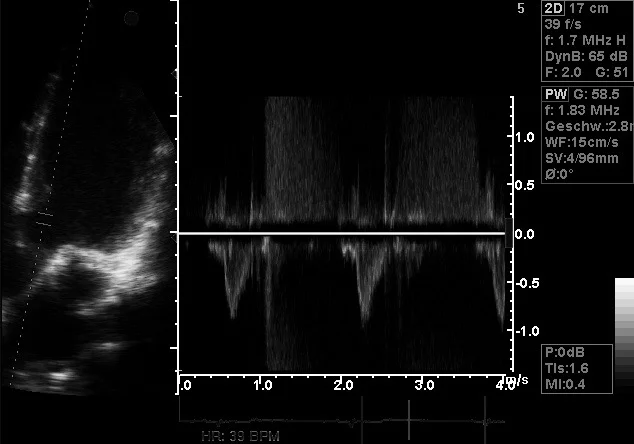

Echokardiographie

• Echokardiographie

(Ultraschall des Herzen)